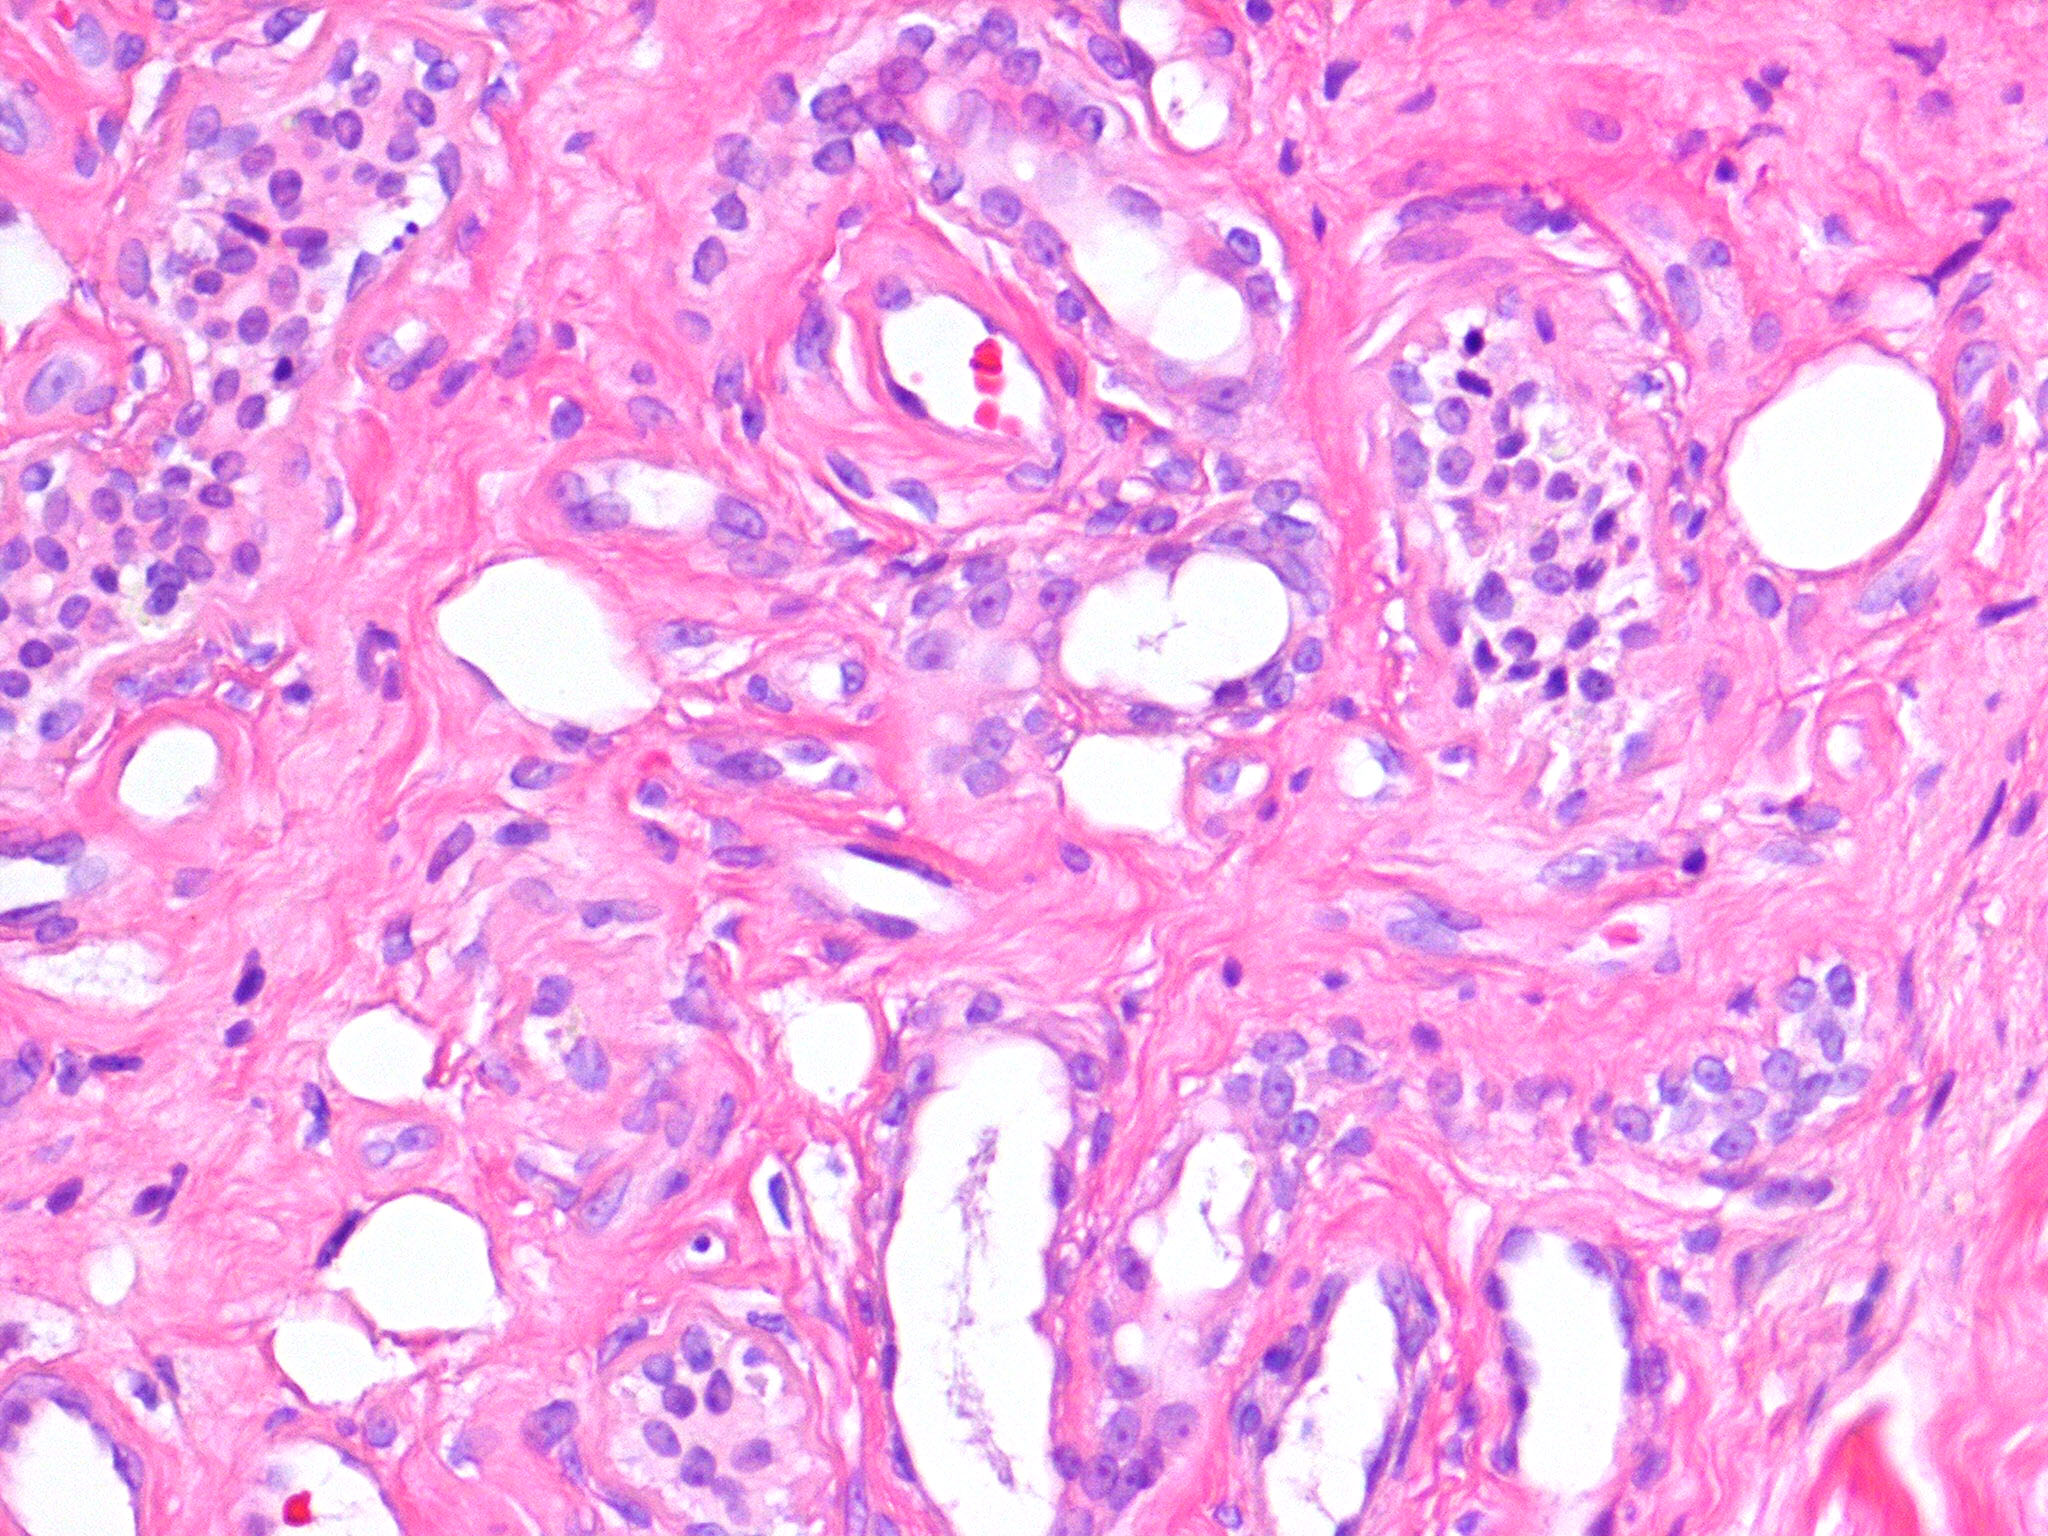

Eccrine angiomatous hamartoma = ورم عجائبي وعائي وناتح

OLYMPUS DIGITAL CAMERA